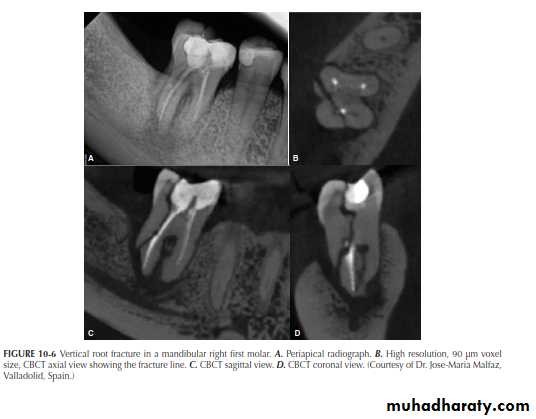

A major advantage of CBCT is the visualization of anatomic

structures in three planes, generally referred to as coronal, axial (transverse), and sagittal reconstructions. CBCT technology also allows for panoramic and oblique reconstructions in addition to anatomic-specific reformatting such as temporomandibular joint (TMJ) improved the sensitivity and specificity of accurately detecting lesions or conditions affecting the jaws

Currently, CBCT imaging is generally recommended for endodontic cases in which conventional dental radiographs may not yield adequate information